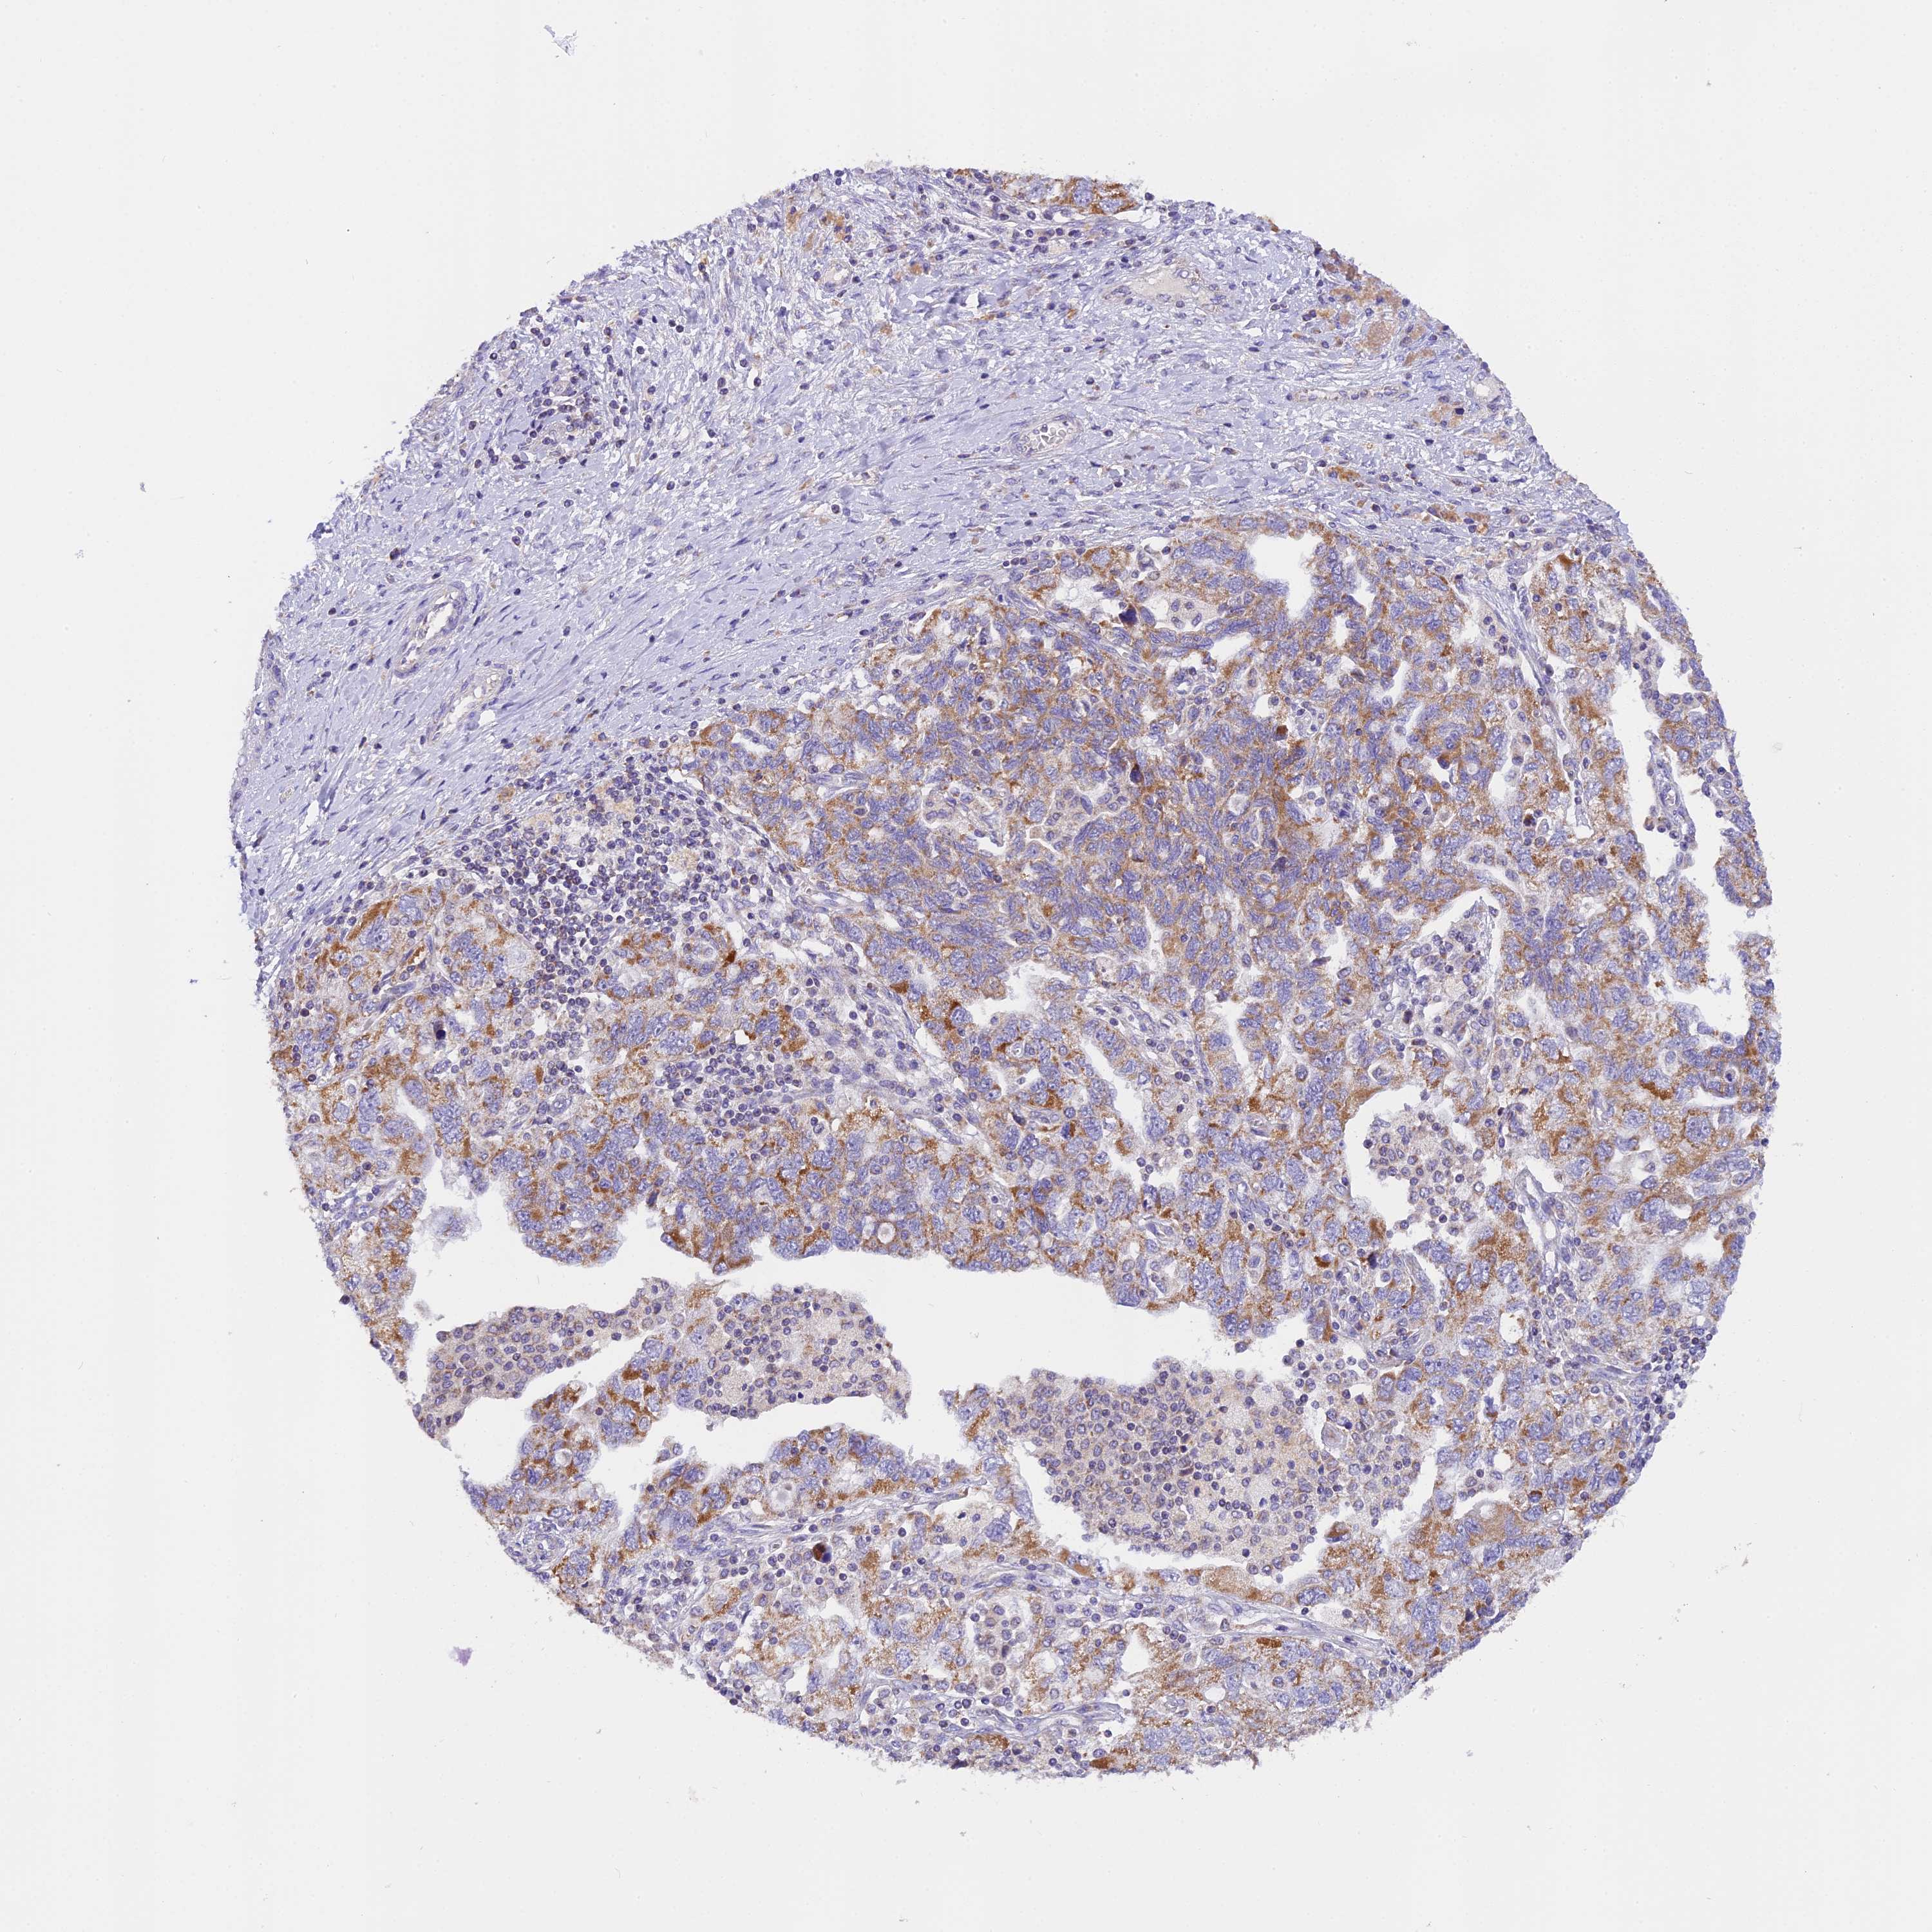

OVARIAN CANCER - Protein expressioni

A mouse-over function shows sample information and annotation data. Click on an image to view it in a full screen mode. Samples can be filtered based on level of antibody staining by selecting one or several of the following categories: high, medium, low and not detected. The assay and annotation is described here.

Note that samples used for immunohistochemistry by the Human Protein Atlas do not correspond to samples in the TCGA dataset.

Antibody stainingi

Antibody staining in the annotated cell types in the current human tissue is reported as not detected, low, medium, or high. This score is based on the staining intensity and fraction of stained cells.